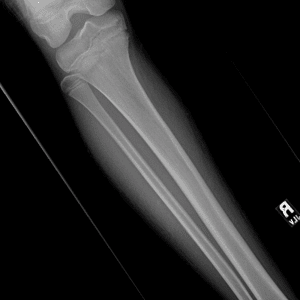

Pediatric Radiographs